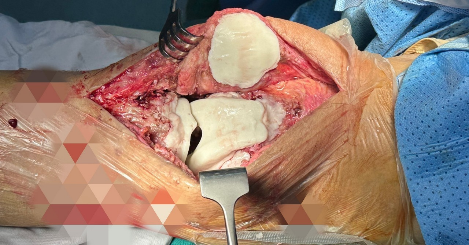

– XQuang: Có hình ảnh khớp gối nhân tạo.

Hình 2. Xquang khớp gối thường quy

Hình 3. Khuôn khớp gối

– Ngày 14/01/2024; BN được phẫu thuật điều trị giai đoạn đầu tiên, khớp xi măng trộn kháng sinh được đúc tại chỗ nhờ sử dụng khuôn đúc trước đó sau khi đo đạc dựng hình tạo khuôn theo khuôn khớp gối của người bệnh.

Hình 4. Khớp gối xi măng chứa kháng sinh